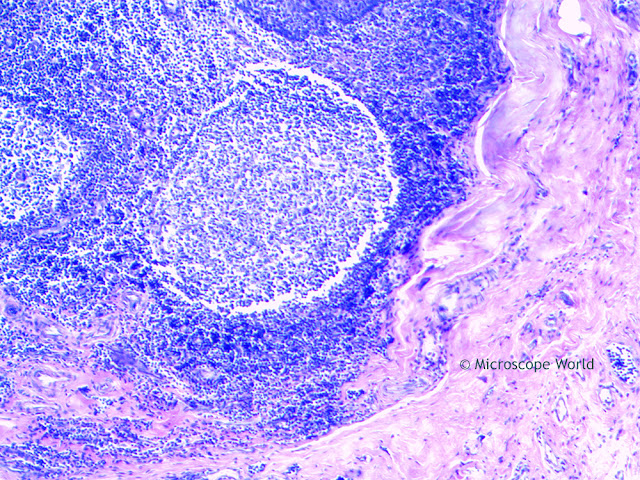

The images below are cross sections of Palatine Tonsils that were captured using a biological lab microscope and a microscopy camera.

| Palatine tonsil under the compound microscope at 40x. |

| Palatine tonsil under the compound microscope at 100x. |

| Palatine tonsil under the compound microscope at 400x. |